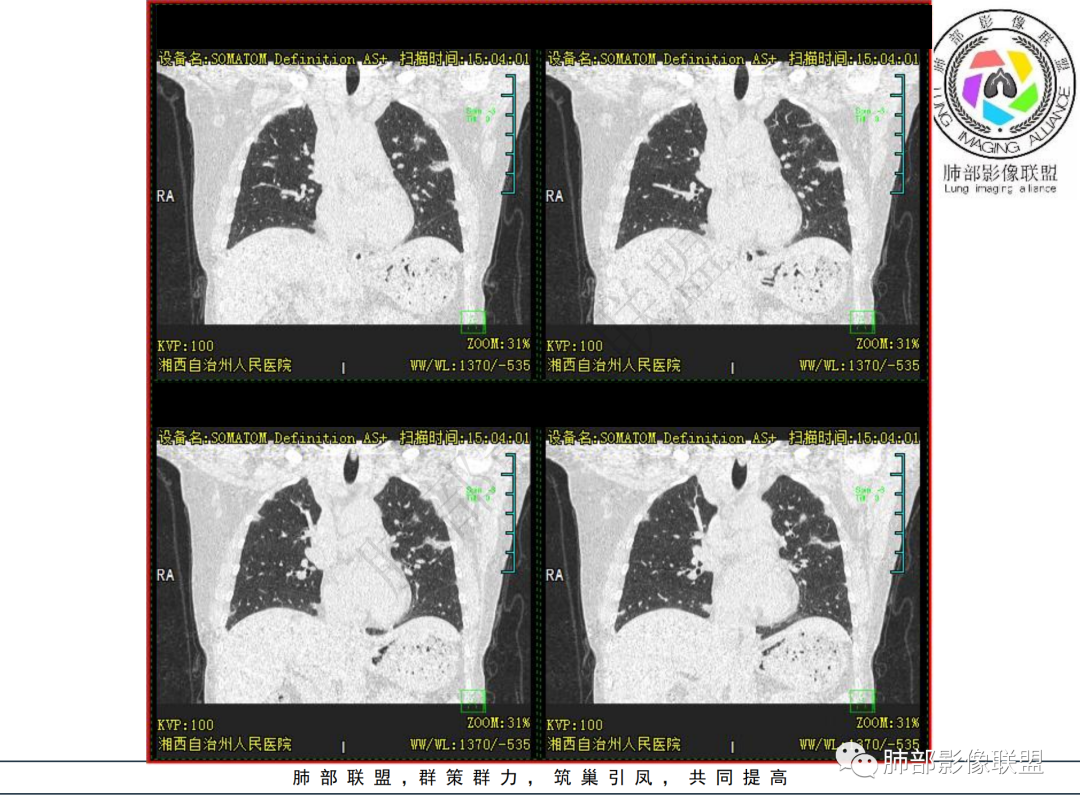

中年妇女,类风湿性关节炎病史,RF升高,感染性指标正常,双肺散在多发结节、斑片、条片灶,边缘欠清晰,大部分胸膜下分布,部分反晕,考虑RA-ⅠLD ,OP样改变

中年女性,有类风湿关节炎病史,双肺内及胸膜下见多发结节,条索状及小实变影,部分结节病灶垂直支气管血管束生长,部分结节病灶内见偏心性空洞形成,病灶收缩力弱,病灶形态多样,部分可见纤维化样改变,整体符合Op表现,结合患者病史,考虑类风湿结节,隐球菌感染不能排除。

中年女性,类风湿关节炎病史,双肺散在结节影,胸膜下分布为主,部分可见小空洞影,部分可见索条影,OP样改变,考虑类风湿结节,鉴别隐球菌

双肺散在多发结节及斑片,边缘欠清晰,胸膜下分布为主,部分内可见支气管扩张,妇女,类风湿性关节炎病史,RF升高,感染性指标正常,考虑RA-ILD,鉴别淋巴瘤。

双肺多发斑片影、结节影,胸膜下分布为主,部分沿支气管血管束分布,病灶大部分边缘平直。

双肺多发结节状及斑片状不均质磨玻璃病灶,胸膜下分布为主,边缘有收缩、凹陷,部分反晕,病灶内可见支气管扩张。中年女性,类风湿关节炎,感染指标正常。类风湿结节?隐球菌?

女,49岁,类风湿因子升高,影像双肺斑片及小结节影,胸膜下分布为主,部分病灶内支气管扩张,双侧胸膜增厚,复查病灶增多增大,考虑RA_ILD。

女性,49岁,多关节肿痛1年余。RF升高。胸部CT:双肺多发斑片影、结节影,胸膜下为主,部分沿支气管血管束分布,大小不等,部分病灶内支气管扩张,部分呈反晕,部分呈楔形宽基底贴附胸膜,复查CT进展,考虑:CTD—ILD?OP?鉴别血管炎、HP、肺梗、曲霉等。

中年女性,多关节肿痛一年,类风湿因子增高,双肺及胸膜下可见多发大小不一结节,部分呈楔形,以胸膜下分布为主,边缘平直,部分病灶分布于支气管血管束,部分可见空气支气管征、反晕征,复查病灶进展,类风湿结节?OP?

胸部CT提示双肺多发的斑片实变结节影,磨玻璃。病灶分布以双肺胸膜下为主,部分病灶以支气管血管素分布,病灶内可见支气管穿行。总体符合间质性肺疾病。

2.双肺多发片状影,胸膜下分布为主,部分沿支气管血管束分布,边界不清,实性及磨玻璃密度,趋于柔和,可见支气管进入或穿行,未见空洞、钙化及树芽等。部分病灶显示反晕。